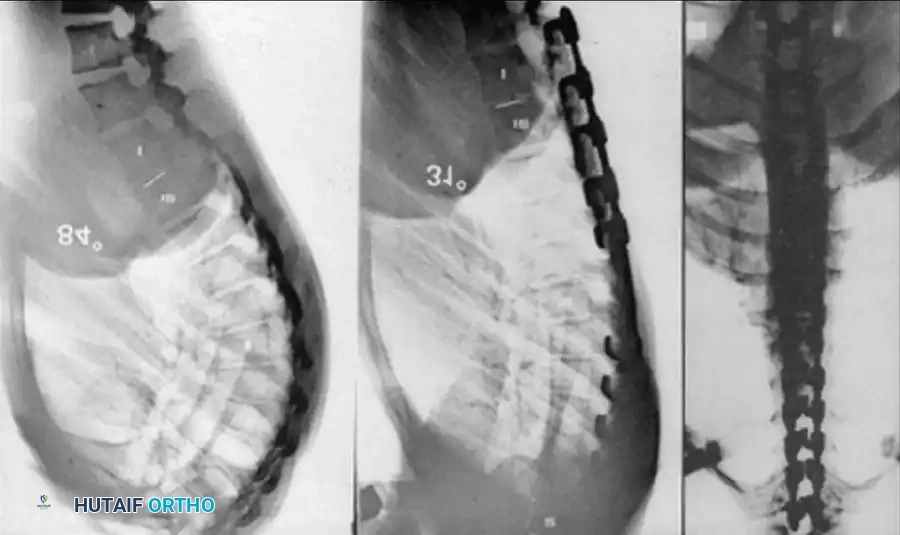

Two-year-old child with type I congenital kyphosis

Posterior column shortening A

Posterior column shortening B

Posterior column shortening C